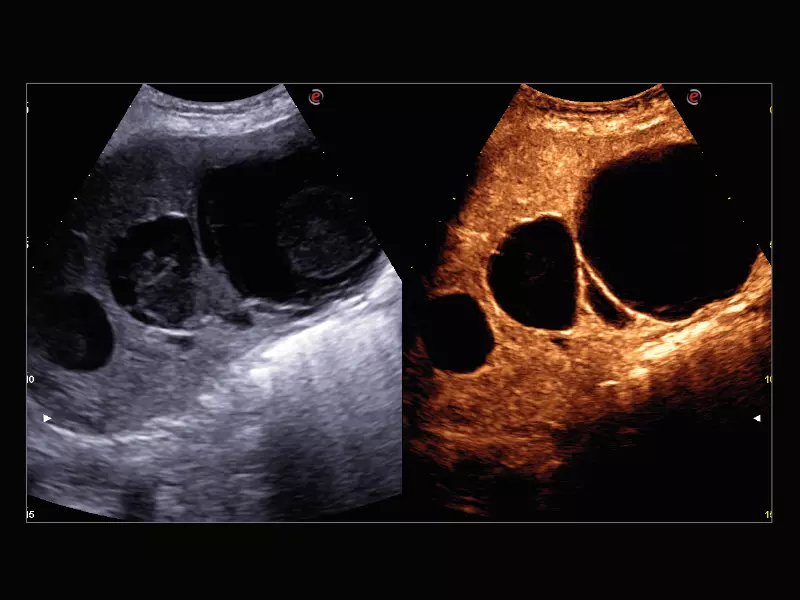

MyLab™E80 - CEUS - Liver

MyLab™E80 - CEUS - Liver